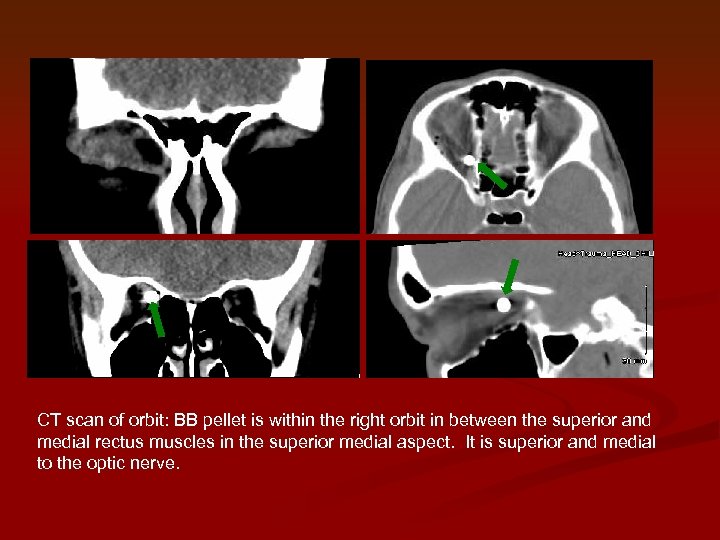

CT scan of orbit: BB pellet is within the right orbit in between the CT scan of orbit: BB pellet is within the right orbit in between the superior and medial rectus muscles in the superior medial aspect. It is superior and medial to the optic nerve.

Superior rectus BB Medial rectus Optic nerve CT scan of orbit: BB pellet is Superior rectus BB Medial rectus Optic nerve CT scan of orbit: BB pellet is within the right orbit in between the superior and medial rectus muscles in the superior medial aspect. It is superior and medial to the optic nerve.